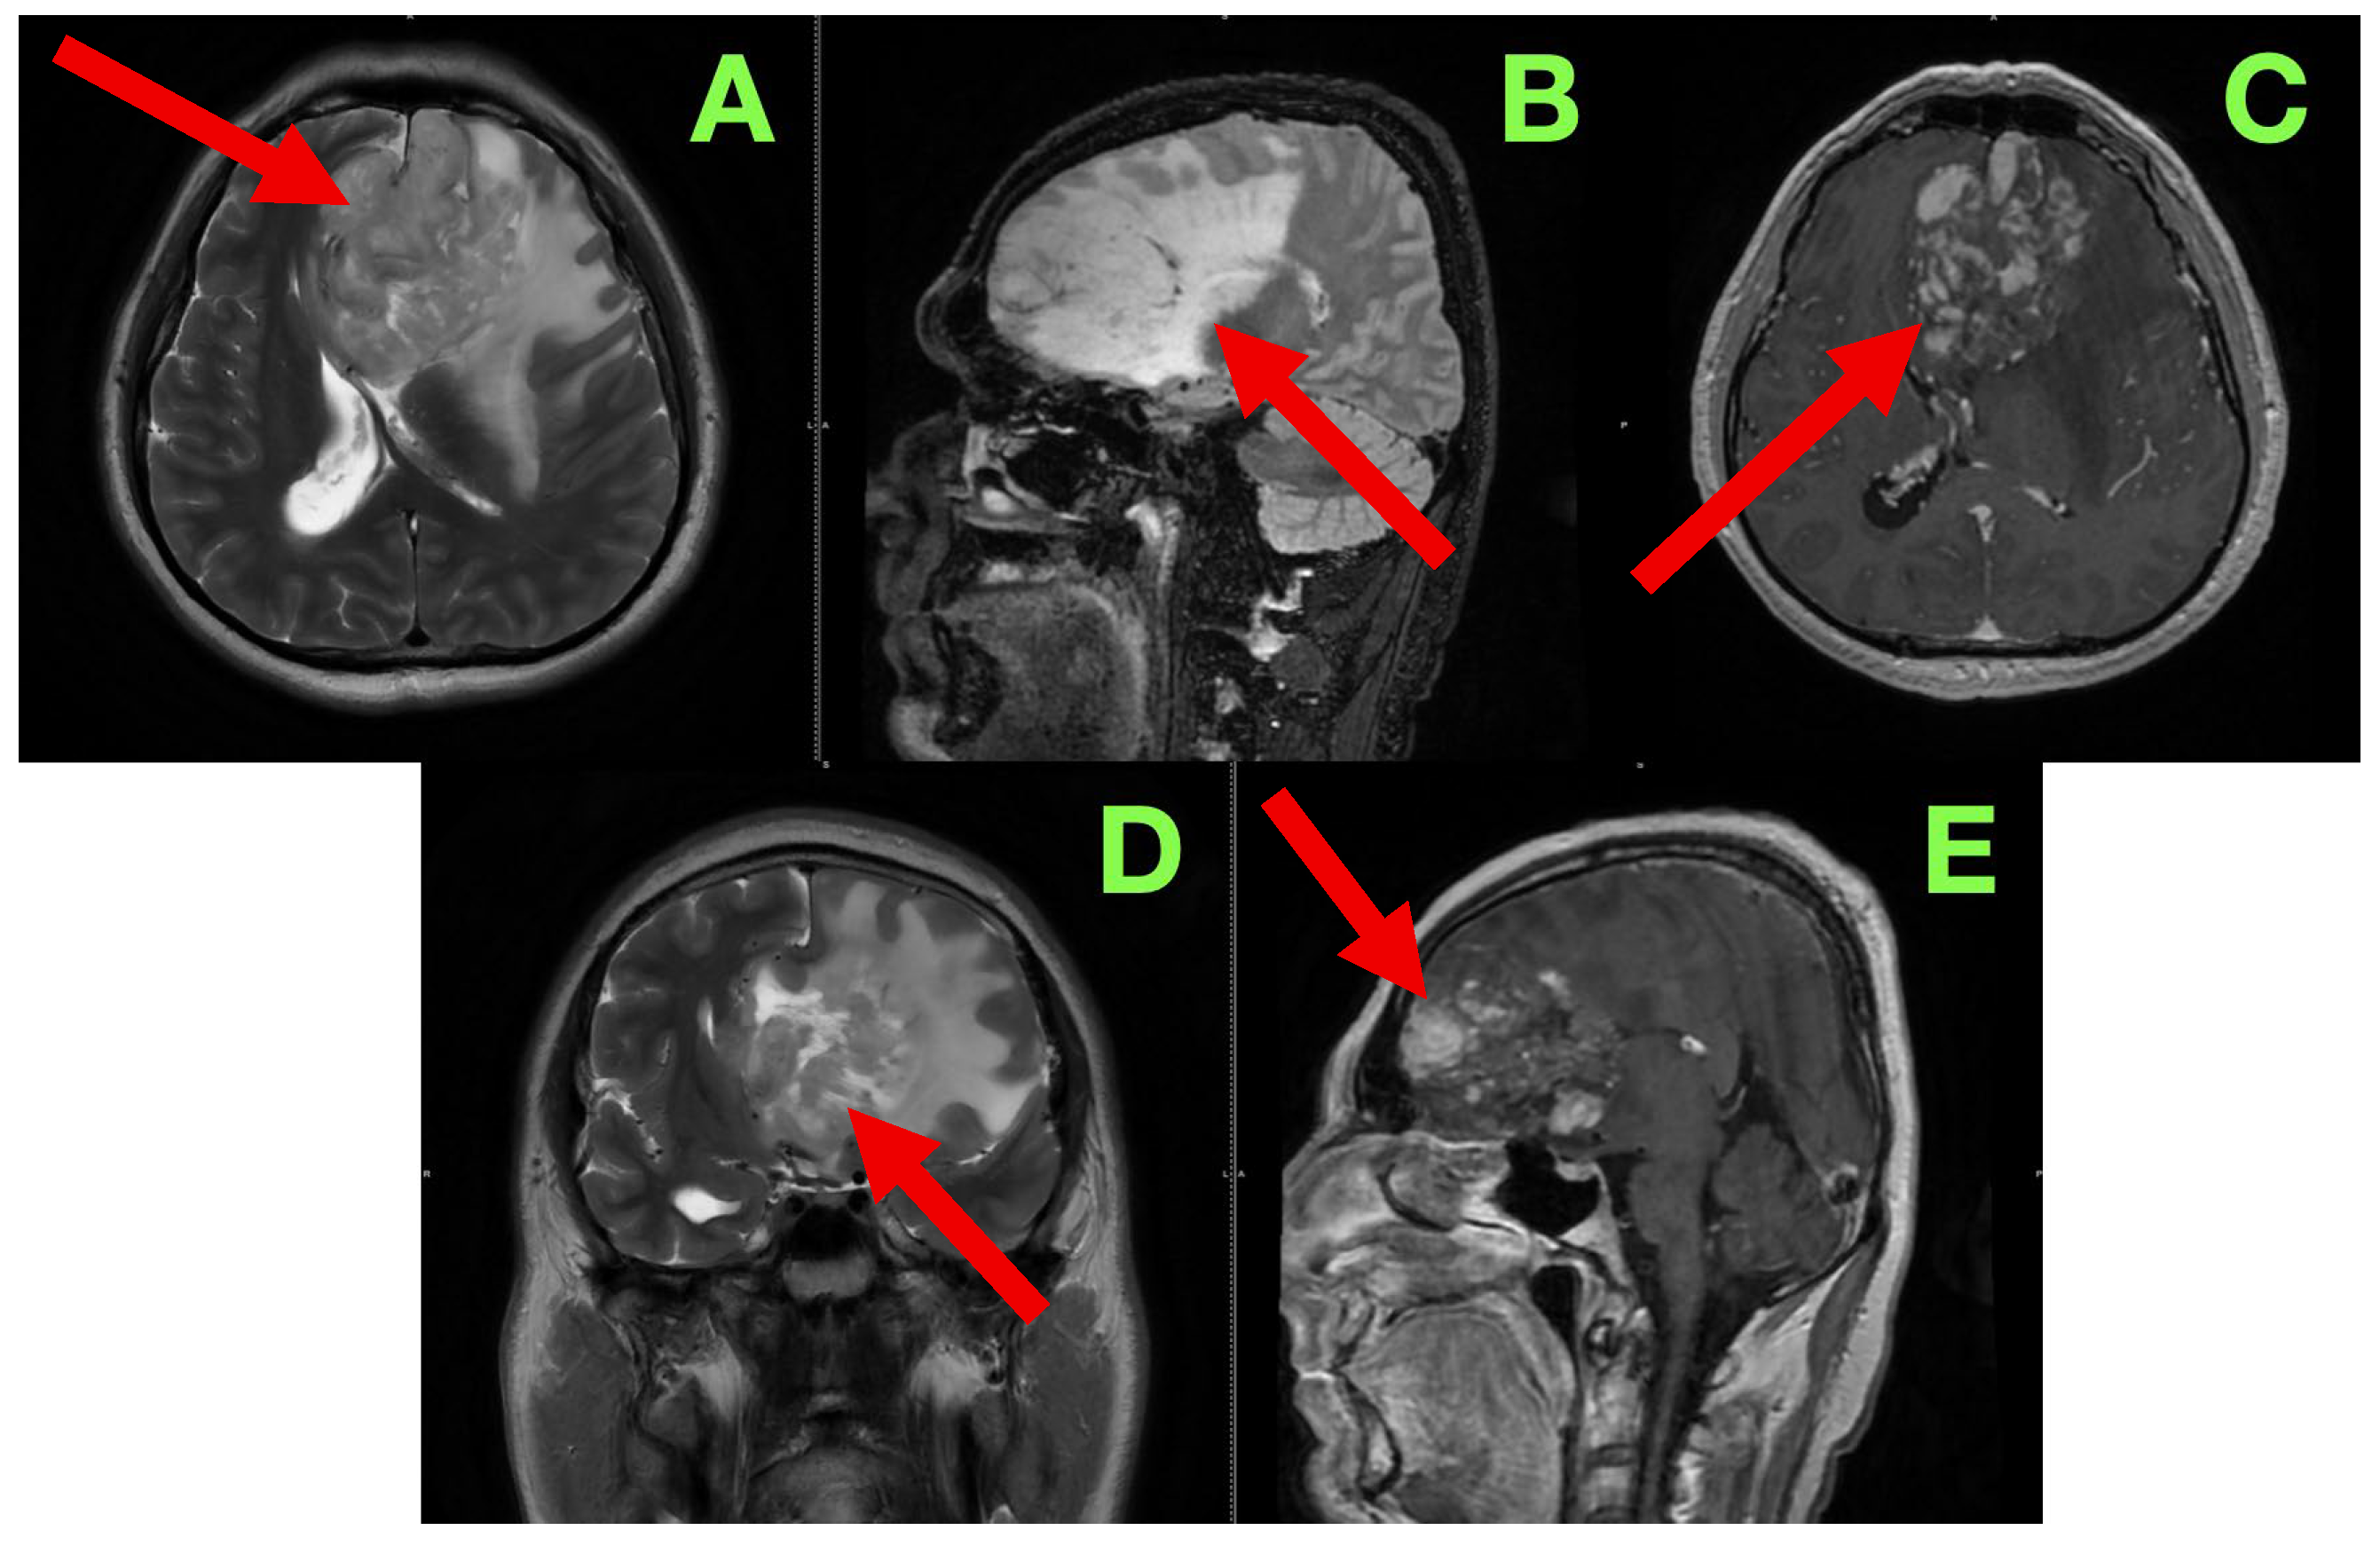

The patient was admitted for further diagnostic workup, seizure prophylaxis, and early surgical planning. Contrast-enhanced magnetic resonance imaging (MRI) (Figure 1) was immediately scheduled to characterize the lesion’s size, location, vascular behavior, potential infiltration of eloquent structures, and operability.

In order to better characterize the lesion and its relationship to eloquent brain structures, we performed a contrast-enhanced cranial MRI following commonly accepted practices and standard high-resolution protocol, which included T1-weighted, T2-weighted, FLAIR, and post-contrast T1 sequences, acquired in the axial, sagittal, and coronal planes. Our goal was to evaluate not only the lesion in terms of size and morphology, but patterns of infiltrative growth, behavior of contrast, edema in the perilesional area, and any early signs of herniation or distortion of local tissue—all useful information in formulating a surgical approach. The study showed a large intra-axial lesion, centrally located in the left inferior frontal lobe, extending medially across the interhemispheric fissure, and abutting potentially or involving structures including the genu of the corpus callosum, anterior cingulate gyrus, and the subcallosal area. The heterogeneity of the lesion suggested infiltrative or infiltrating capacity, with indistinct margins and associated mass effect on surrounding gyri and white matter tracts. In the axial sequences on T2-weighted images (Figure 1A), the lesion exhibited heterogeneous hyperintensity, made up of heterogeneous, irregular, infiltrative borders. The lesion extended from the inferior frontal gyrus into the middle frontal gyrus (pars triangularis and opercularis), with evidence of perilesional signal change indicating vasogenic edema, extending inferiorly from the deep portions of the frontal lobe into the critical centro-semiovale, frontal horn, and anterior portions of the corona radiata. The left frontal horn of the lateral ventricle was compressed, and a midline shift of approximately 7 mm was observed. There was also some subtle effacement of the left Sylvian fissure and perisylvian cortex evident. The overall findings suggested not only cortical but also MCU of some important white matter tracts, particularly the FAT and pairing superior longitudinal fasciculus (SLF), and potentially less so of the anterior limb of the internal capsule. The sagittal FLAIR images offered further insight regarding vertical and anteroposterior extent of the lesion. There appeared to be deformation of the genu of the corpus callosum as it looked bowed posteriorly and superiorly. Edema extended anteriorly toward the cingulate gyrus and there was narrowing of the interhemispheric fissure. The lesion was clearly in contact with the subcallosal area and there appeared borderline indistinctness from the gyrus rectus and the olfactory sulcus as well as possible involvement of ventromedial prefrontal regions. The basal cisterns were patent but due to evident asymmetries in midline structures, likely early subfalcine shift was occurring. Axial post-contrast T1-weighted images (Figure 1C) showed multifocal nodular enhancement but without any significant or well-formed ring enhancement or associated central necrosis. Areas of contrast uptake were seen at the superior and medial margins of the lesion and there was an area extending towards the callosal–cingulate junction. These findings could represent frank blood–brain barrier disruption and absent necrotic transformational features. There was importantly no enhancement of the ependyma or ventricular dissemination or leptomeningeal spread. Coronal T2-weighted images (Figure 1D) confirmed inferior extent of the lesion and effacement towards the orbitofrontal cortex and adjacent anterior insula. There was good correlation of sulcal effacement to these areas. The finding appeared to laterally displace the medial frontobasal cisterns, and surrounding edema was located toward the limen insulae. These findings raised the question of possible subpial invasion with respect to language relevant structures in the perisylvian area. Beyond the limitations of the axials, the sagittal post-contrast T1 (Figure 1E) images also demonstrated blurring between the cortical–subcortical transition in the convexity of the frontoorbital region and focal enhancement along the gyral surfaces, perhaps indicative of either superficial cortical spread or diffuse perivascular pathology. Spatially, the observed enhancement was patchy and irregular—reasonably suggestive of an infiltrative neoplastic process, but not specific. There were no signs of enhancement of the basal meningeal layers or of infratentorial structures. The third and fourth ventricles were symmetric and non-dilated.

Read in conjunction with the clinical presentation, the radiologic findings shaped our impression of an infiltrative high-grade glioma—most likely a GBM (IDH-wildtype). Out of an abundance of caution with diagnosis, we also considered the option of an anaplastic astrocytoma, as well as the potential for secondary transformation of a lower-grade glioma, and, with the least likelihood, primary CNS lymphomas or tumefactive demyelinating lesions, given the absence of necrosis and ring enhancement. The degree of mass effect and the nature of the enhancement noted seemed excessive relative to contrast uptake, which we reasoned as representing a high-grade glioma likely to have diffuse infiltrative behavior with minimal central breakdown.

The involvement of the dominant inferior frontal gyrus, in particular, with adjacent extension in and around regions absolutely necessary for speech initiation and fluency, aligns with the patient’s presentation of non-fluent aphasia. Also, even the surrounding edema encroaches toward the anterior limb of the internal capsule. This correlates with the positive right-sided corticospinal findings on examination. Additionally, we were concerned about the radiologic appearance suggesting ‘early’ subfalcine herniation. That said, at this phase, there was no evidence of distortion of the brainstem structures or uncal shift.

Figure 1. Pre-operative magnetic resonance imaging of the brain. (A): Axial T2-weighted image showing a heterogeneously hyperintense, poorly marginated intra-axial lesion (red arrow) centered in the left inferior frontal gyrus, with extension into the middle frontal gyrus and deep white matter. Marked vasogenic edema effaces cortical sulci, compresses the left lateral ventricle, and produces a midline shift of approximately 7 mm. (B): Sagittal FLAIR sequence demonstrating tumor extension into the subcallosal area (red arrow), with superior displacement and anterior bowing of the genu of the corpus callosum. Narrowing of the interhemispheric fissure and blurring of adjacent gyri indicate early subfalcine herniation. (C): Axial post-contrast T1-weighted image revealing patchy, nodular enhancement (red arrow) at the superomedial margin of the lesion, without central necrosis or ring formation. This enhancement pattern suggests partial disruption of the blood–brain barrier, typical of an infiltrative glial process. (D): Coronal T2-weighted image demonstrating inferior tumor extension into the frontoorbital cortex and anterior insula (red arrow). Associated asymmetric edema exerts mass effect on the anterior cerebral artery territory. The left frontal horn is compressed, and medial structures are displaced. (E): Sagittal post-contrast T1-weighted image showing faint, non-uniform gyriform enhancement (red arrow) along the frontobasal convexity, with blurring of the cortical–subcortical junction. No infratentorial involvement or leptomeningeal enhancement is present.